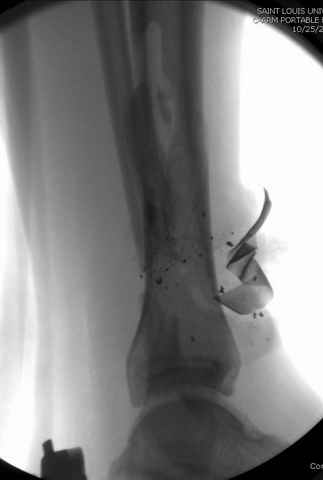

На снимках варианты фиксации малоберцовой:

№ 2-5 при огнестрельном переломе

№ 6-11 при pilon percutaneus fixation